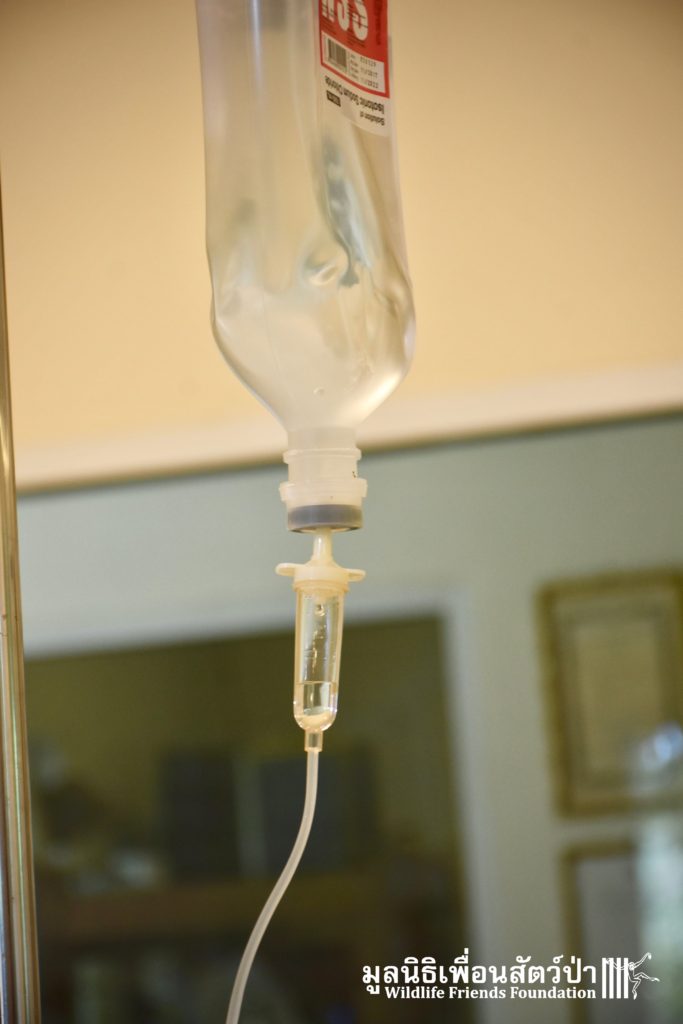

Recently the WFFT Wildlife Hospital Rescue Team were called by a local woman working at Khao Yoi Temple about a female long-tailed macaque who fell from a tree and could not move. The macaque in question had a young infant so the situation was even more urgent. When the Rescue Team arrived on site, they found a poor monkey laying in a gutter. The woman who called us and kept an eye on the injured mother macaque told us the baby was now holding onto another female that we could see walking away with the infant. She was in bad condition. Fast breathing, almost unanimated, the Vet Team decided to give her a light sedative to ensure her safety.

This temple is inhabited by a large population of macaques. Since the rescue team arrived they were observing the situation, many of the monkeys took an interest in what the team were doing, they needed to act fast to avoid any conflict with the concerned monkeys. Once the monkey had been transported to the rescue vehicle, the decision has been made to take her to a clinic to take on x-ray to access her further. The X-ray didn’t reveal any major broken limbs, just a small fracture on a toe but because had big secreting fluid from the anus, the vet decided to ask for further examinations.

She was not doing well and her body was showing that she had some internal problem. With the ultrasound scan, the trauma has been identified: gas and blood clot in her lungs and bladder. She was too unstable. No possible surgery. With only 50% chance of making it she was taken to the WFFT Wildlife Hospital for further treatment. Sadly, a few hours after arriving she passed away. Her injuries were too severe and she was inoperable. Internal bleeding took her away. Rest in peace little one.